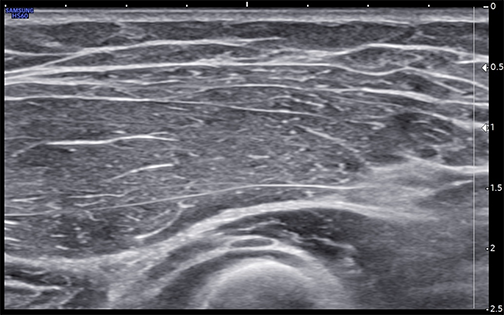

Unlabeled short-axis ultrasound image of the deep motor branch of the radial nerve at the arcade of Frohse.

Unlabeled short-axis ultrasound image of the deep motor branch of the radial nerve a few millimeters distal to the arcade of Frohse.